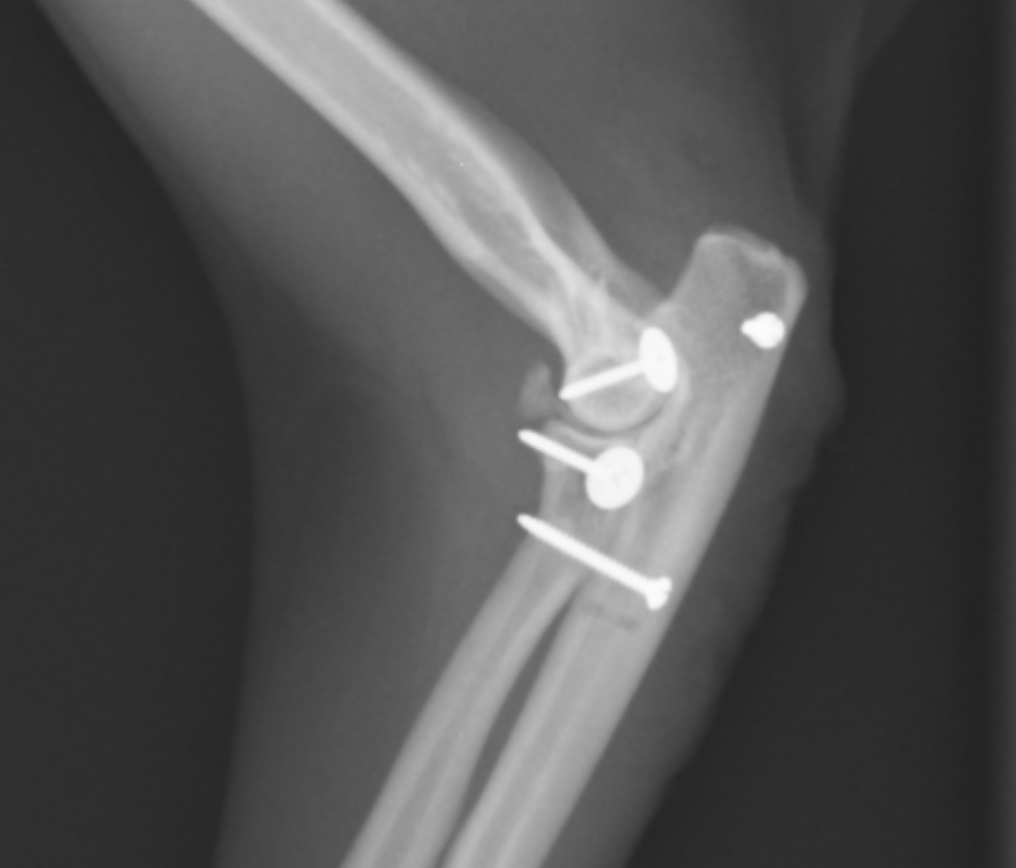

こちらが患肢の横から見たX線です。紫が上腕骨で、オレンジが橈骨、緑が尺骨です。このX線だと、上腕骨と橈尺骨が離れているのが分かると思います。橈骨と尺骨の脱臼はよくわかりません。

この黄色の矢印のスクリューが尺骨と橈骨を固定しています。

次に上腕骨と橈骨を結ぶ側副靭帯を再建します。アンカーと呼ばれるスクリューをうち、そこに黄色で書いた位置に人工靭帯を結びます。

最後に上腕骨と尺骨を結ぶ靭帯を再建します。実際にはこのような靭帯は存在しませんが、ここを締結することで脱臼しにくくなります。

最終的なX線画像です。ずれていた橈骨尺骨上腕骨がピッタリとあっているのが分かると思います。小さな骨片が見られますが、ここの脱臼の場合このような小骨片がかけてしまうことがよくあります。